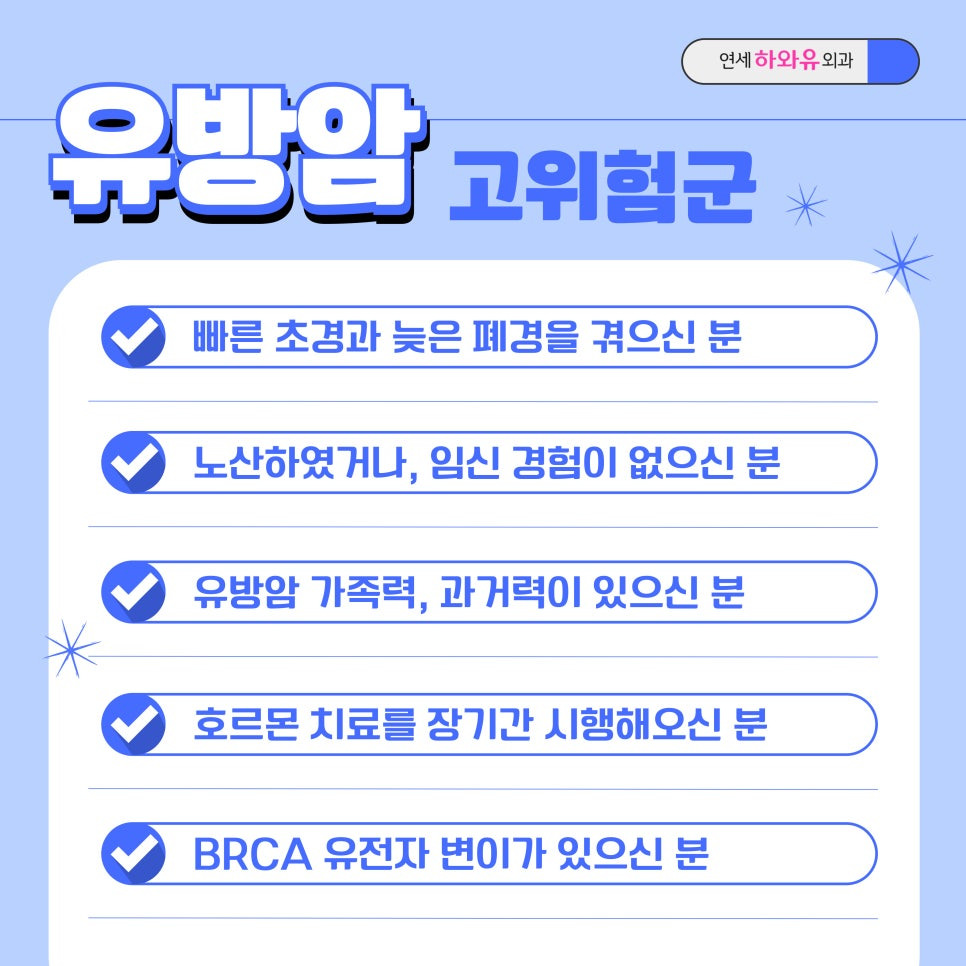

주의해야 할 유방암 고위험군

유방암의 명확한 원인은 밝혀지지 않았지만, 초경이 빠르거나 폐경이 늦은 경우 유방암 고위험군에 속합니다.

특히 유전적으로 유방암 가족력이 있는 경우에는 정기적인 유방검진이 필수이며, 출산 경험이 없거나 늦은 나이에 첫 출산을 한 경우에도 유방암에 걸릴 확률이 높은 편입니다. 흡연, 과도한 음주를 즐기시는 분은 유방암의 위험을 높일 수 있는 생활 습관이므로 주의가 필요합니다.

유방암 고위험군에 속하시는 분이라면 특별한 증상이 없어도 6개월~1년에 한 번씩 정기 검진을 받는 것은 유방 건강을 지키는 데 도움 될 수 있으므로 참고해 주시길 바래요.